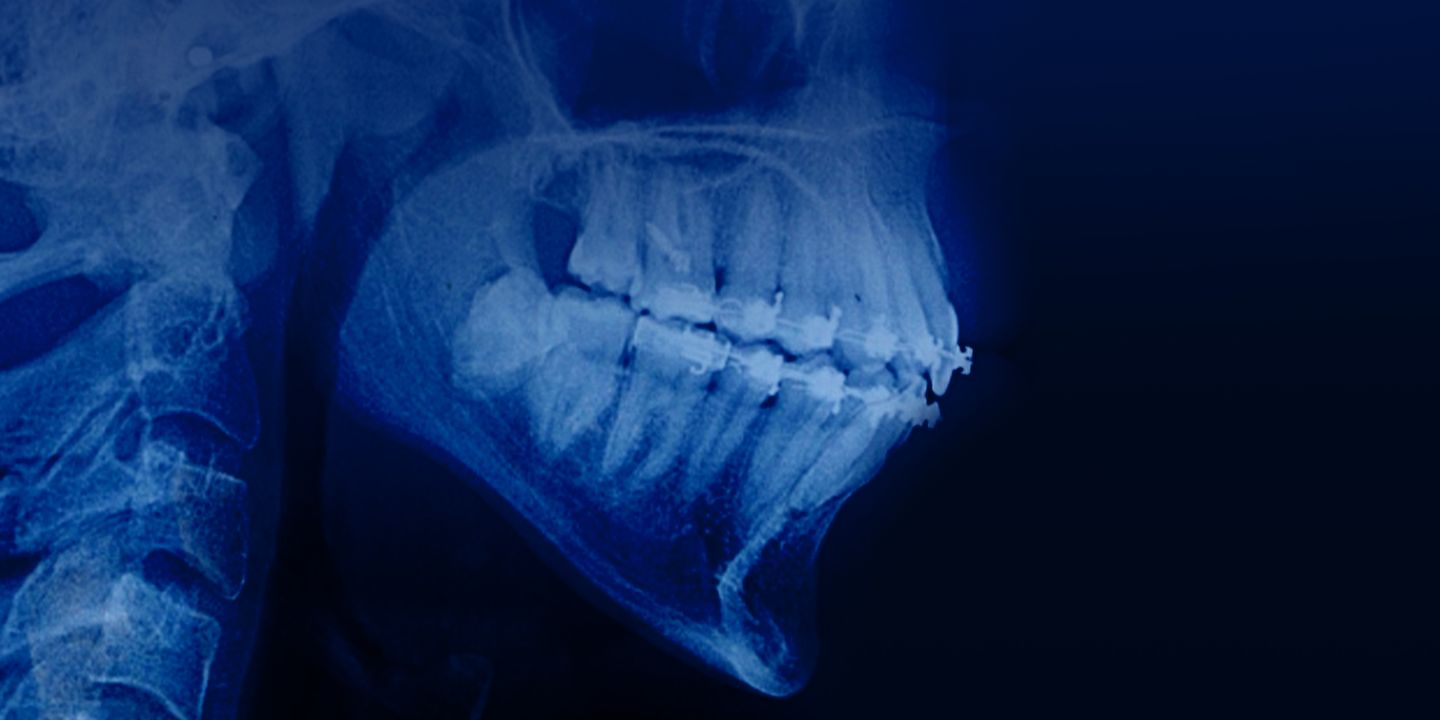

Orthodontic treatment in patients with periodontal and alveolar bone pathology

New online course for orthodontists on how to perform orthodontic treatment in patients with periodontal and alveolar bone pathology.

Within the course will be discussed:

– Light orthodontic forces when moving teeth in adult patients

– Space creation prior to implantation

– bodily tooth movement into an extraction space

– Relative and true tooth intrusion

– The use of aligners in adult patients

– Using Damon system in adult patients.